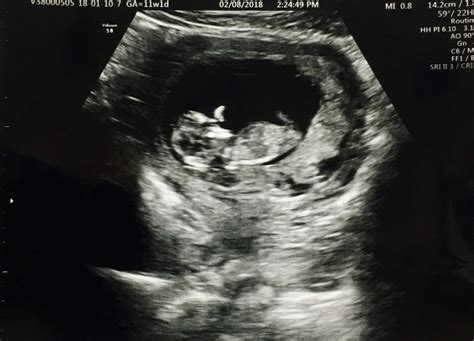

An 11 weeks pregnant ultrasound is typically performed as part of routine prenatal care. This ultrasound is often referred to as the "nuchal translucency" scan. It is usually conducted between 10 weeks and 13 weeks and 6 days of pregnancy. The primary goal of this ultrasound is to assess the baby's development and screen for certain chromosomal abnormalities, such as Down syndrome.

• Visualization of the Baby: At 11 weeks, your baby is about the size of a fig, measuring approximately 1.6 inches (4.1 centimeters) in length and weighing around 0.25 ounces (7 grams). The ultrasound will show the baby's head, body, and limbs, although the details will be more pronounced in later ultrasounds.

• Nuchal Translucency Measurement: This measurement assesses the fluid-filled space at the back of the baby's neck. Increased fluid in this area can indicate a higher risk of chromosomal abnormalities.

• Other Structures: The ultrasound may also visualize the baby's spine, stomach, and other internal structures, providing a comprehensive view of your baby's development.